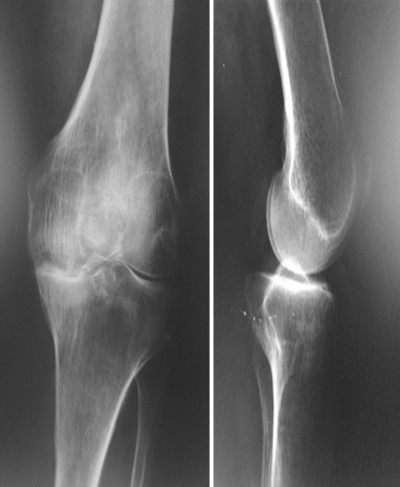

Приклад 1. Хвора Б. 52 років. Діагноз: Ревматоидній Деформівний IVст. гонартроз, вальгусна деформація колінногосуглоба.  Нестабільність та руйнування компонентів ендопротеза. Хворій виконано ревізійне ендопротезування: видалення компонентів ендопротезу, виявлений дефект латерального  виростку великогомілкової кістки тип Т3А за класифікацією АОRI [G.A. Engh, C.H. Rorabeck, 1997]. Під час операції виконана кісткова пластика дефекту латерального виростка лівої великогомілкової кістки. Використаний ендопротез колінного суглоба з подовжувачами .

Приклад 2. Хвора  М. 68 років. Діагноз: лівобічний деформівний IVст. гонартроз, стан після ТЕП лівого КС (2014р.). Під час виконання оперативного втручання компоненти ендопротезу встановлені в варусному положенні. Асептична нестабільність компонентів ендопротеза, тотальна  нестабільність зв’язкового апарату компонентів колінного суглоба (2017 р.)  Хворій виконано ревізійне ендопротезування: видалення компонентів ендопротезу, виявлений дефект виростку великогомілкової кістки тип Т2А за класифікацією АОRI [G.A. Engh, C.H. Rorabeck, 1997]. Враховуючи стан зв’язкового апарату використаний зв’язаний ендопротез типу Hinch.

Приклад 3. Хвора К. 52 років. Діагноз: Деформівний IVст. гонартроз, стан після ТЕП лівого КС (2013р.). ІМТ хворої складає 35 балів. Асептична нестабільність компонентів ендопротеза лівого колінного суглоба, міграція великогомілкового компоненту (2017 р.) (рис. 2 а). Хворій виконано ревізійне ендопротезування: видалення компонентів ендопротезу, виявлений дефект медіального виростку великогомілкової кістки тип Т3А за класифікацією АОRI [G.A. Engh, C.H. Rorabeck, 1997]. Під час операції виконана кісткова пластика дефекту. Використаний ендопротез колінного суглоба з подовжувачами.

Приклад 4. Хвора Г. 72 років. Діагноз: Деформівний IV ст. гонартроз, стан після ТЕП КС (2010р.). Гемартроз в післяопераційному періоді, хронічний синовііт.Септична нестабільність компонентів ендопротеза  колінного суглоба на протязі року. Виявлений дефект виростків стегнової кістки  тип Т3, F 3 за класифікацією АОRI [G.A. Engh, C.H. Rorabeck, 1997]. Хворій виконано  двоєтапне ревізійне ендопротезування: видалення компонентів ендопротезу іплантовано спейсер з антибіотиком. Піcля санаціїї виконано другий єтап певізії, імплантовано ревізійний ендопротез колінного суглоба.